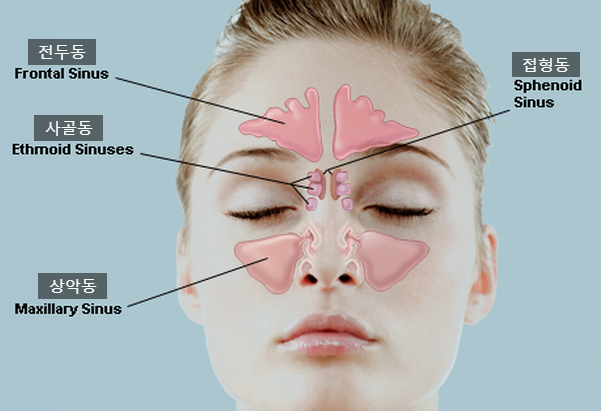

1. 급성 부비동염의 원인은 무엇인가요? ? 1) 급성 비염 – 급성 부비동염의 가장 흔한 원인으로 비점막의 바이러스나 세균 감염이 상악동 점막으로 전이되었을 때 발생 2) 치과 감염 – 충치나 발치로 인한 염증의 확산으로 인한 급성 상악동염3 ) 외상 – 골절 및 안면 외상은 출혈이 축적되어 감염에 취약해질 수 있습니다. 4) 해부학적 폐색 – 해부학, 비강 및 부비동으로 인한 외이구의 환기 및 배액은 할러 낭종, 중격 만곡, 수술 후 유착과 같은 문제를 줄입니다. 5 ) 악안면 기형 – 구개열, 후문 폐쇄증 6) 상기도 감염 – 편도선염, 인두염 및 기타 상기도 감염 7) 전신 상태 – 영양 결핍, 장기간의 스테로이드 치료, 조절되지 않는 당뇨병, 혈액 질환, 화학 요법 등 8) 원발성 섬모 운동 이상증 9) 기타 – 비용 비강 폴립, 이물질, 포장, 오염된 물에서 수영 Johnson & Johnson – 부비동염이란 무엇입니까? 2. 급성 부비동염과 관련된 병원성 박테리아는 무엇입니까? ? 1) 바이러스 – 약 50%의 바이러스에 의해 발생 – Rhinovirus, Parainfluenza, Echovirus, Coxsackievirus, Respiratory Syncytial Virus 등 2) 세균 – Streptococcus pneumoniae, Haemophilus influenzae, Mora catarrh Bacteria 등 칸디다증, 아스페르길루스증 – 전신 쇠약 환자, 당뇨병, 면역억제제 장기 사용 SinusCure – 바이러스성 또는 세균성 부비동 감염? 차이점이 뭐야? 삼. 급성 부비동염의 증상은 무엇인가요? 상안검 부종 및 내안각 압통 – 급성 사골동염 : 비측 및 안구 심부에 통증, 안구를 움직일 때 통증 심화 – 급성 접형동염 : 안구 심부, 후두부, 두정엽, 측두부 통증 2) 누런 가래, 코막힘 – 증상은 1~2주 정도 지속됨 – 콧물은 노란색에서 녹색으로 나타나며 악취가 동반될 수 있음 3) 기침, 가래, 인후통 – 상기도와 유사한 증상 감기에 걸리는 감염 4) 안구주위 증상 – 안구로 인해 부비동염으로 구성되어 있어 안구 주변 부종을 일으킬 수 있음 – 부비동염의 합병증으로 실명에 이를 수 있음 5) 전신증상 – 발열, 권태감, 무기력 등 6) 소아 부비동염 – 아이들은 부비동염의 전형적인 두통을 거의 호소하지 않습니다 – 7일 이상 지속되는 감기와 같은 증상, 밤에 악화되는 기침, 미열 및 콧물 DrJockers.com – 부비동 감염: 원인, 증상 및 자연 지원 전략4. 급성 부비동염은 어떻게 진단됩니까? 부종, 점액, 화농성 분비물에 주의하고 압통 확인 – 인두 검사 중 점액이 인후 뒤쪽으로 흐르는 후비루(PND) 확인 Thumbay Hospital Day Care – 비강 진단에 대해 알아야 할 사항 내시경3 ) 영상진단 (1) 단순방사선검사(X-ray) ① Water view: 상악동이 뚜렷하게 보이는 Radiopaedia – 좌측: 안면골(Waters view), 우측: 급성 상악동염 ② Caldwell view: 사골동이 선명하게 보이는 Radiopaedia – 좌측 : 두개골(Caldwell view), 우: 급성 상악동염 ③ 측면도: 접형동과 전두동이 선명하게 보임 좌: 영상의학과 – 상악동과 안면골(측면), 우: Medscape – 상악동염(sinusitis) 영상화 (2) 상악동의 CT 부비동(PNS CT) – 합병증이 있거나 의심되는 경우, 당뇨나 면역결핍 등의 동반질환이 있는 경우, 약물치료로 증상이 호전되지 않는 경우, 종양이 의심되는 경우, 안면구조에 수술이 필요한 경우 변형되고 비정상적인 부비동 20155년 7월, 치료받은 점막 리슈만편모충증 환자의 다중 검출기 컴퓨터 단층 촬영 스캔. 급성 부비동염 비염) 치료할 수 있습니까? ? 1) 항생제 치료 – 적절한 항생제를 충분한 시간 동안 투여 – amoxicillin 또는 amoxicillin + clavulanic acid Augmentin(augumentin) 5~10일 – macrolide clarithromycin 2차 약제로는 azithromycin 사용 – quinolone계 levofloxacin 또는 ciprofloxacin을 2차로 선 – 2차 선으로 세팔로스포린 사용 – 혐기성 세균이 의심되는 경우 메트로니다졸 또는 클린다마이신 사용* 적절한 항생제 투여로 48~72시간 이내에 임상 증상 호전, 증상 소실 후 최소 3~7일 항생제 투여* 총 권장 치료 기간은 10일에서 3주 이상 위키하우 – 항생제 없이 사는 법 부비동염 없애기 페스티벌: 점막을 수축시켜 부비강의 배액과 환기를 개선하기 위해 사용, 3일 이내 사용 – 항히스타민제: 상기 요인이 있는 경우 사용 가능 알레르기성 비염 – 진통제: 환자의 통증 완화에 사용 – 진정기침 거담제: 부비강의 분비물 배출을 돕는다 3) 상악동 세척 – 상악동 세척으로 상악동 세척으로 치료하여 상악동의 염증성 분비물을 배출하고 환기를 깨끗하게 한다. 감염, 전신 상태 및 해부학적 이상을 바로잡아야 합니다. 5) 수술 – 합병증이 발생하거나 임박한 경우 – 환자가 심한 통증을 호소하거나 적절한 항생제로도 통증이 악화되는 경우 수술을 고려합니다. 코. 위와 매우 유사합니다. . ! 축농증이 의심되는 경우에는 정밀한 신체검사가 필요하기 때문에 최대한 의사에게 알리는 것이 좋습니다! ! 무엇을 하느냐가 차이점 중 하나라고 할 수 있겠네요^^ 긴 글 읽어주셔서 감사하고, 다음 시간에는 “만성 부비동염”에 대해 함께 알아보도록 하겠습니다! 부비동염 = 부비동염 = 비염 + 부비동염 / 급성 부비동염 여러분 안녕하세요! 닥터동동이고 돌아왔습니다! ! 오늘은 흔히 ‘부비동염’이라고 부르는데… blog.naver.com